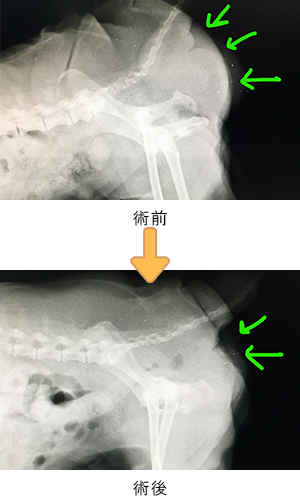

身体検査で臀部の膨らみを確認。触診・画像検査で腸と前立腺の会陰部脱出が認められた。

| 会陰ヘルニアは、高齢の未去勢の雄犬に多い疾患です。会陰(お尻の周囲)部の筋肉間がゆるんで腹部臓器がお腹の中から皮下にとび出して(ヘルニア)しまう病気です。 この症例は、腸、膀胱、前立腺が皮下へとび出しており、もう少しで排尿ができなくなり致命的な状況になるところでした。 本症例は人工メッシュを用いて会陰ヘルニア整復手術を行いました。術後は排便排尿もスムーズにでき、経過も良好です。なお、会陰ヘルニアは再発率が高い疾患であり、術後も日常ケアや経過観察が必要となります。 |